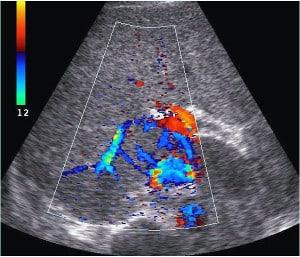

This course presents a series of liver Doppler case studies, focusing on ultrasound techniques to assess liver vascular structures and detect pathologies. Gain insights into the evaluation of portal vein, hepatic artery, and hepatic vein flow, and improve your diagnostic skills in liver-related conditions through real-world case examples.